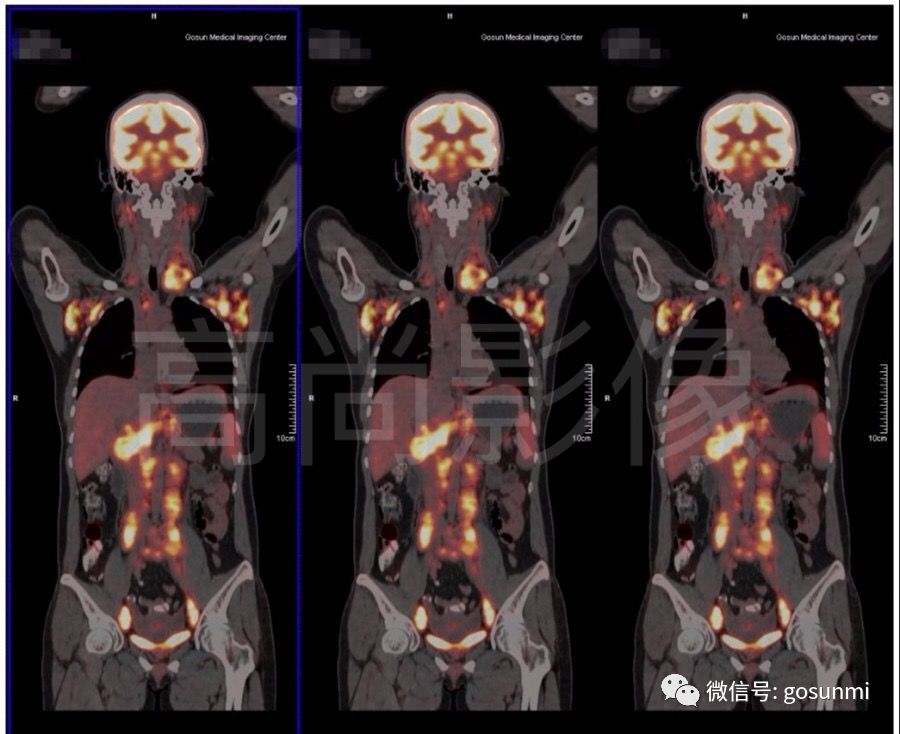

二、淋巴瘤的病變非常廣泛,常常不能準確判斷有淋巴結(jié)腫大的部位是否真的有腫瘤的累及。對于頸部和盆腔的淋巴結(jié)有異常高代謝病灶的情況,PET/CT能夠清楚顯示。因此對于惡性淋巴瘤的患者,尤其是還沒有開始治療的患者,PET/CT可以更加準確的判斷腫瘤的范圍,有利于明確臨床分期和制定治療計劃。

(淋巴瘤化療前)

(淋巴瘤化療后)

三、PET/CT對于惡性淋巴瘤的治療評價有重要作用。在痛苦的數(shù)個療程化療后,體內(nèi)殘留的淋巴結(jié)或淋巴組織是殘留病灶、壞死組織還是纖維組織?這是每位患者及醫(yī)生最關(guān)心的問題,由于PET/CT能夠顯示組織的代謝活性,因此具有比普通CT 具有更好的分辨能力,它能對影像學外觀相似的組織進行鑒別,以辨別是否還有腫瘤組織或細胞存活。